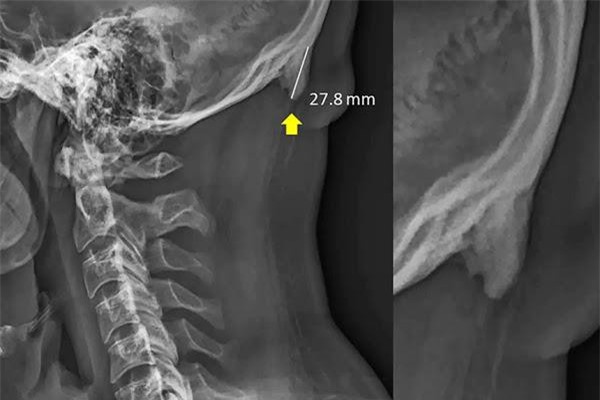

Nghe có vẻ khó tin, nhưng theo một nghiên cứu từ các nhà khoa học Úc, việc liên tục sử dụng smartphone có thể khiến chúng ta mọc một chiếc “sừng” ngay trên hộp sọ.

DNVN - Các nhà khoa học Australia vừa công bố một nghiên cứu gây sốc cho giới trẻ. Theo đó, việc liên tục sử dụng smartphone trong thời gian dài có thể khiến con người mục một chiếc sừng ngay trên hộp sọ.